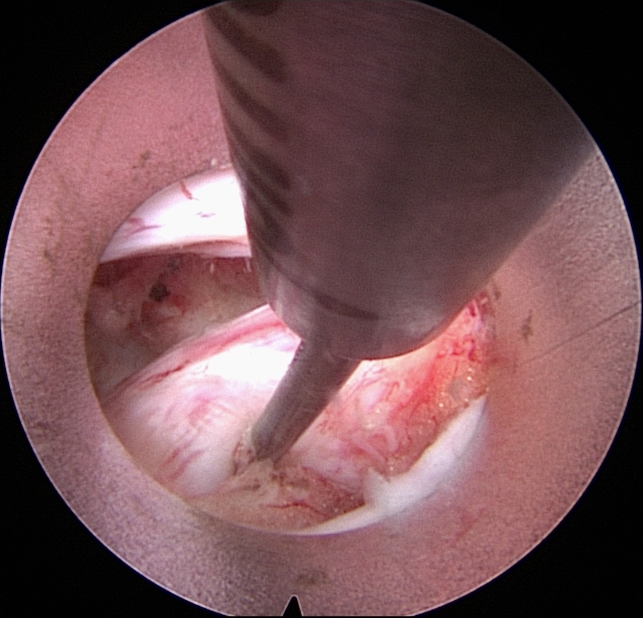

Παρασπονδυλική προσπέλαση

Παρέχει τη δυνατότητα για την αφαίρεση , δισκοκήλης αλλά και αποσυμπίεση του σπονδ. σωλήνα σε περίπτωση σπονδυλικής στένωσης